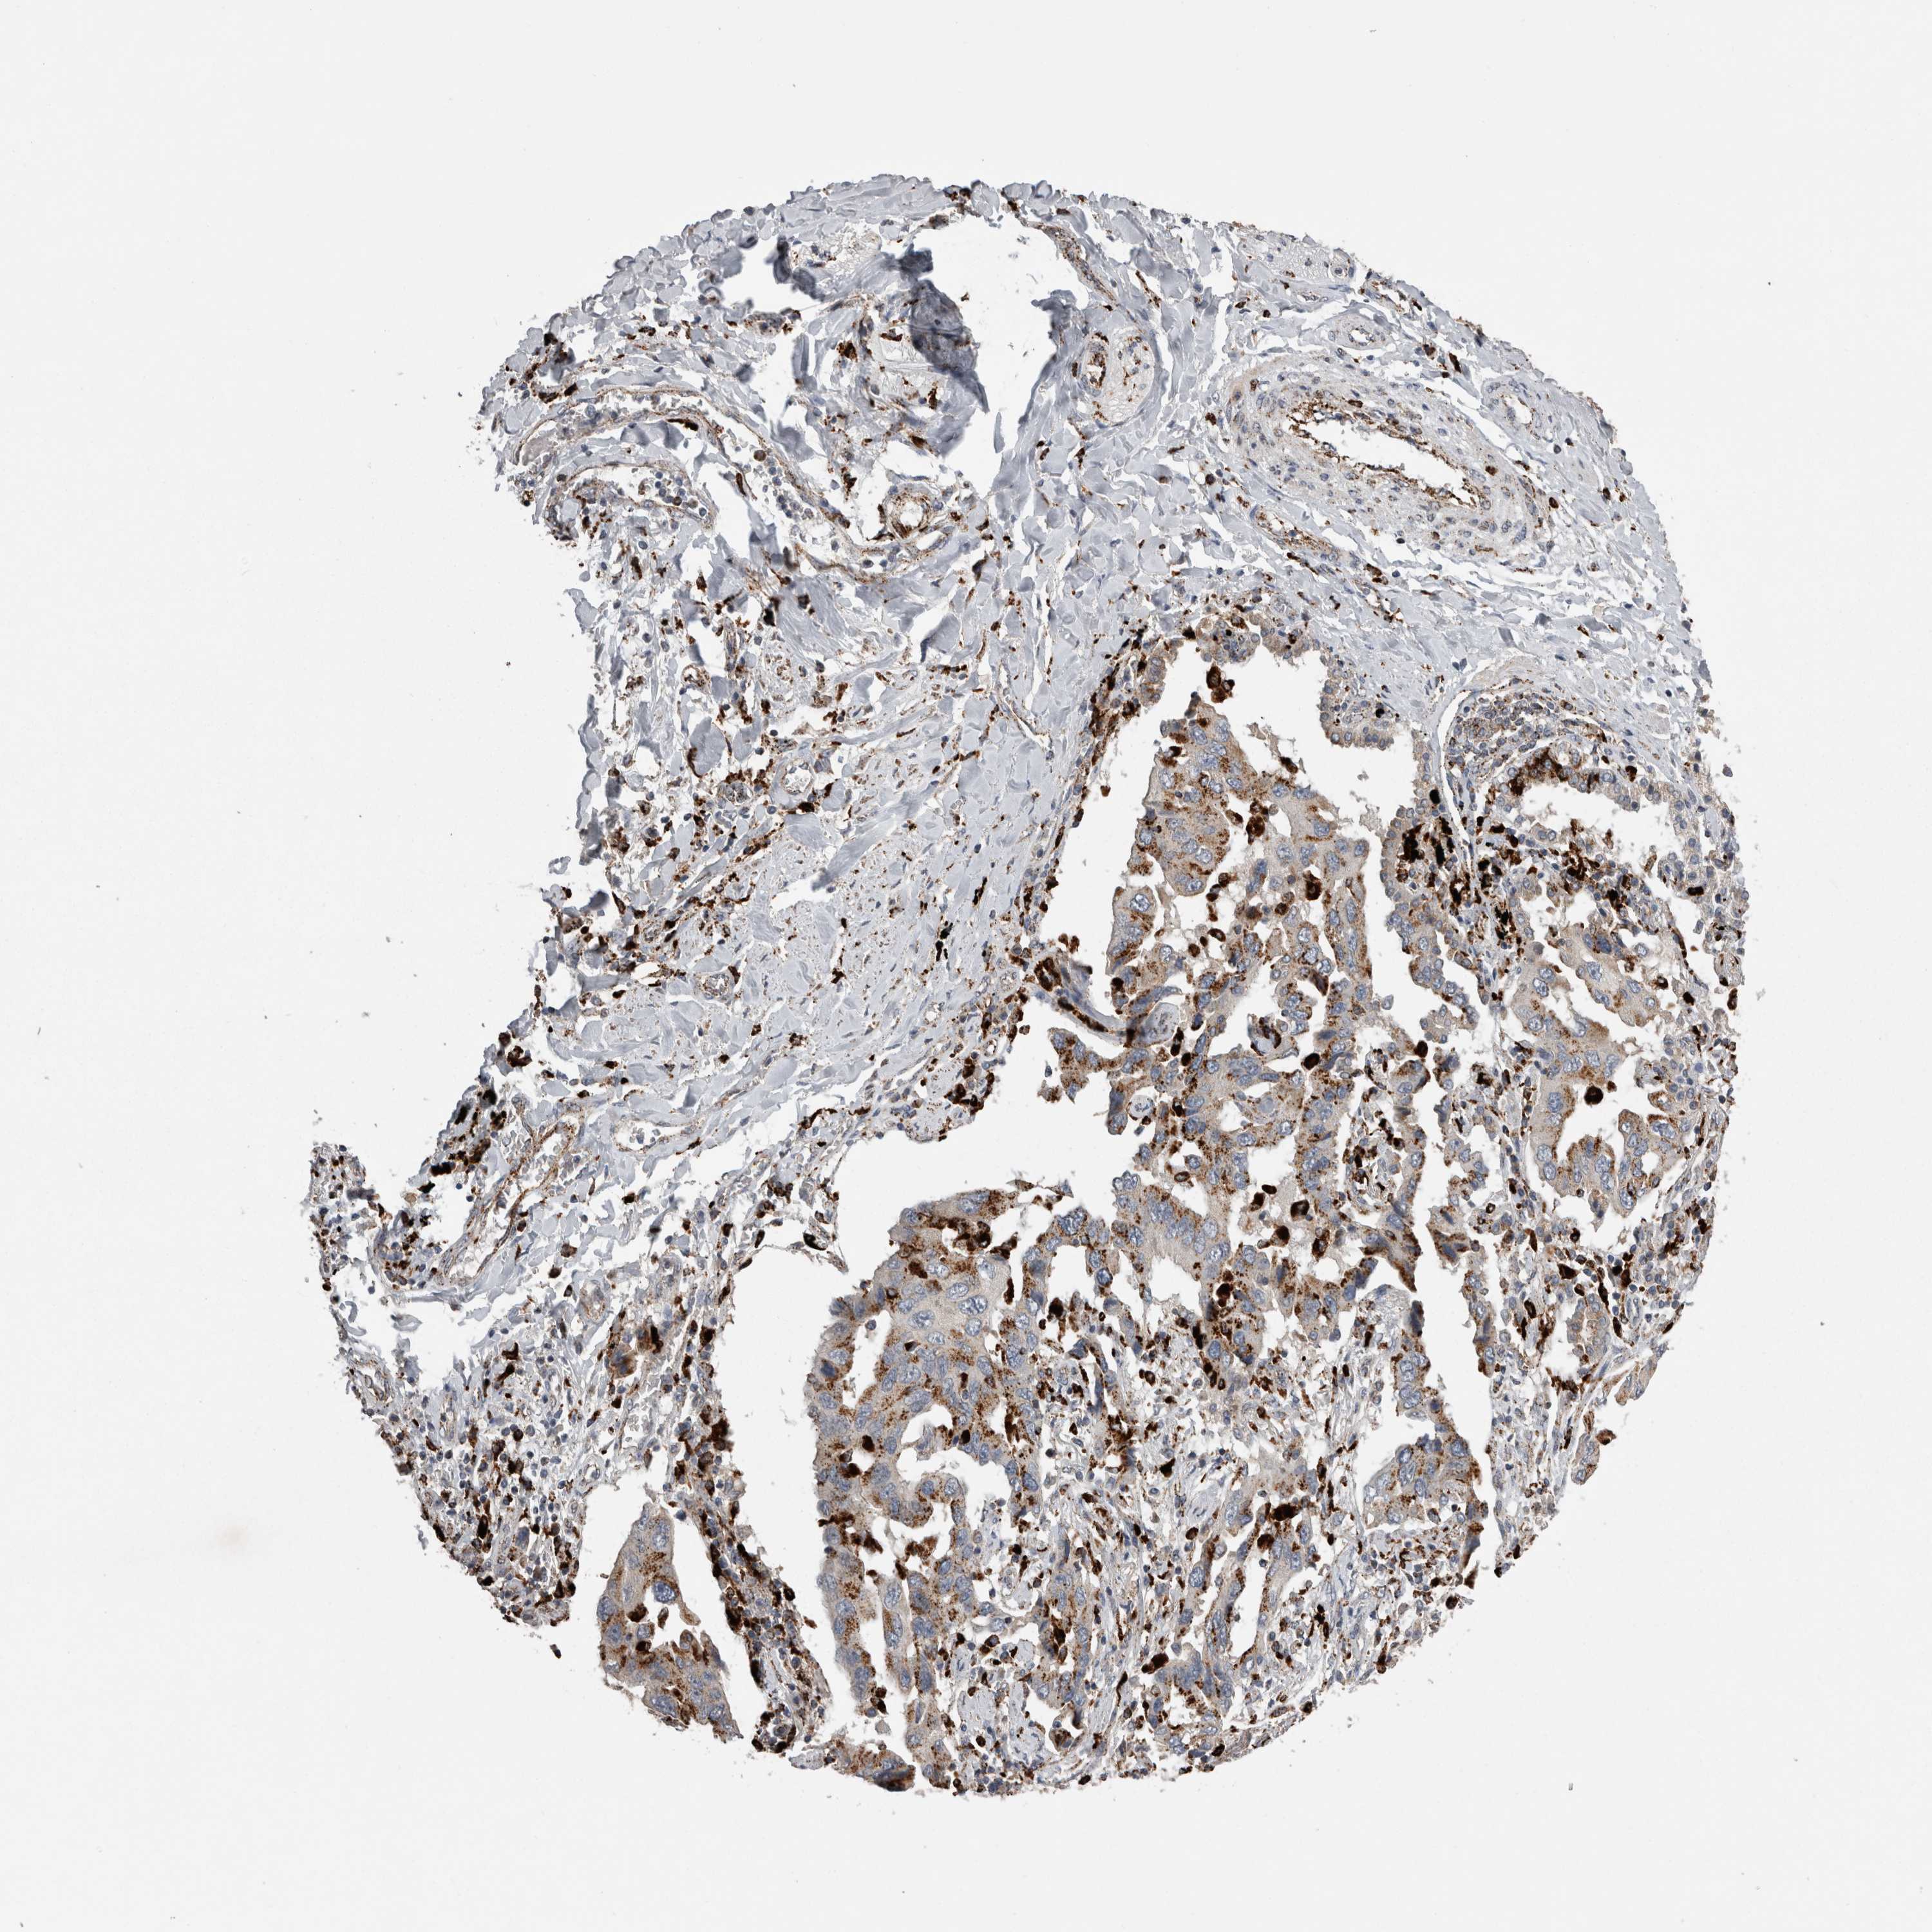

LUNG SQUAMOUS CELL CARCINOMA (TCGA) - Interactive survival scatter ploti

The Survival Scatter plot shows the clinical status (i.e. dead or alive) for all individuals in the patient cohort, based on the same data that underlies the corresponding Kaplan-Meier plots. Patients that are alive at last time for follow-up are shown in blue and patients who have died during the study are shown in red.

The x-axis shows the expression levels (FPKM) of the investigated gene in the tumor tissue at the time of diagnosis. The y-axis shows the follow-up time after diagnosis (years). Both axes are complimented with kernel density curves demonstrating the data density over the axes. The top density plot shows the expression levels (FPKM) distribution among dead (red) and alive patients (blue). The right density plot shows the data density of the survived years of dead patients with high and low expression levels respectively, stratified using the cutoff indicated by the vertical dashed line through the Survival Scatter plot. This cutoff is automatically defined based on the FPKM cutoff that minimizes the p-score. The cutoff can be changed by dragging the vertical line or by entering a cutoff value in the square labeled "Current cut-off".

Under the Survival Scatter plot the p-score landscape (black curve; left axis) is shown together with dead median separation (red curve; right axis). Dead median separation is the difference in median mRNA expression between patients who have died with high and low expression, respectively. It is calculated as follows: median FPKM expression of dead patients with high expression - median FPKM expression of dead patients with low expression. This is intended to aid the user in visually exploring custom cutoffs and the associated p-scores and dead median separation.

Individual patient data is displayed and can be filtered by clicking on one or more of the category buttons on the top of the page. Categories describing expression level and patient information include: high, low, alive, dead, female, male and tumor stages. The scale of the x-axis can be toggled between linear and log-scale by clicking on the "x log" button. Mouse-over function shows TCGA ID, patient information and mRNA expression (FPKM) for each patient.

& Survival analysisi

Kaplan-Meier plots summarize results from analysis of correlation between mRNA expression level and patient survival. Patients were divided based on level of expression into one of the two groups "low" (under cut off) or "high" (over cut off). X-axis shows time for survival (years) and y-axis shows the probability of survival, where 1.0 corresponds to 100 percent.

CTSZ is not prognostic in Lung Squamous Cell Carcinoma (TCGA)

: 255.18